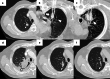

Image-guided percutaneous lung ablation has proven to be a valid treatment alternative in patients with early-stage non-small cell lung carcinoma or oligometastatic lung disease. Available ablative modalities include radiofrequency ablation, microwave ablation, and cryoablation. Currently, there are no sufficiently representative studies to determine significant differences between the results of these techniques. However, a common feature among them is their excellent tolerance with very few complications. For optimal treatment, radiologists must carefully select the patients to be treated, perform a refined ablative technique, and have a detailed knowledge of the radiological features following lung ablation. Although no randomized studies comparing image-guided percutaneous lung ablation with surgery or stereotactic radiation therapy are available, the current literature demonstrates equivalent survival rates. This review will discuss image-guided percutaneous lung ablation features, including available modalities, approved indications, possible complications, published results, and future applications.